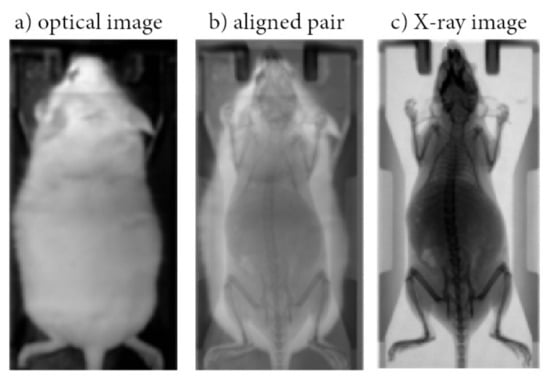

2.1. Data Collection and Preprocessing